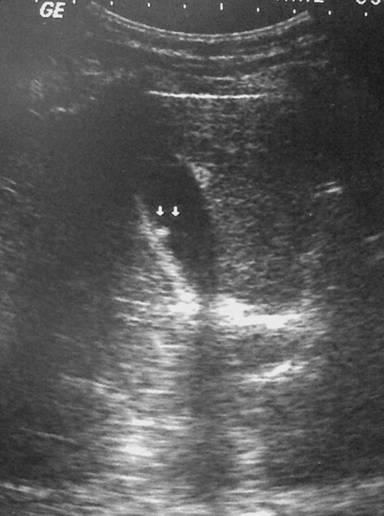

Blood examination, including liver and renal function, was within normal range. Abdominal ultrasound scan showed a small well-defined non-mobile echogenic structure attached to the wall of the gallbladder with no posterior shadowing. The features were suggestive of a gallbladder polyp (Figure 1), but no gallstones were detected.

Figure 1. An echogenic non-mobile structure attached to the gallbladder wall (small arrows) with no posterior shadowing. Features suggestive of a polyp. |